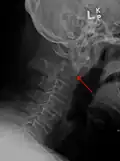

A fracture of the base of the dens as seen on plain X-ray -

Type 3 odontoid fracture -

Type 2 dens fracture